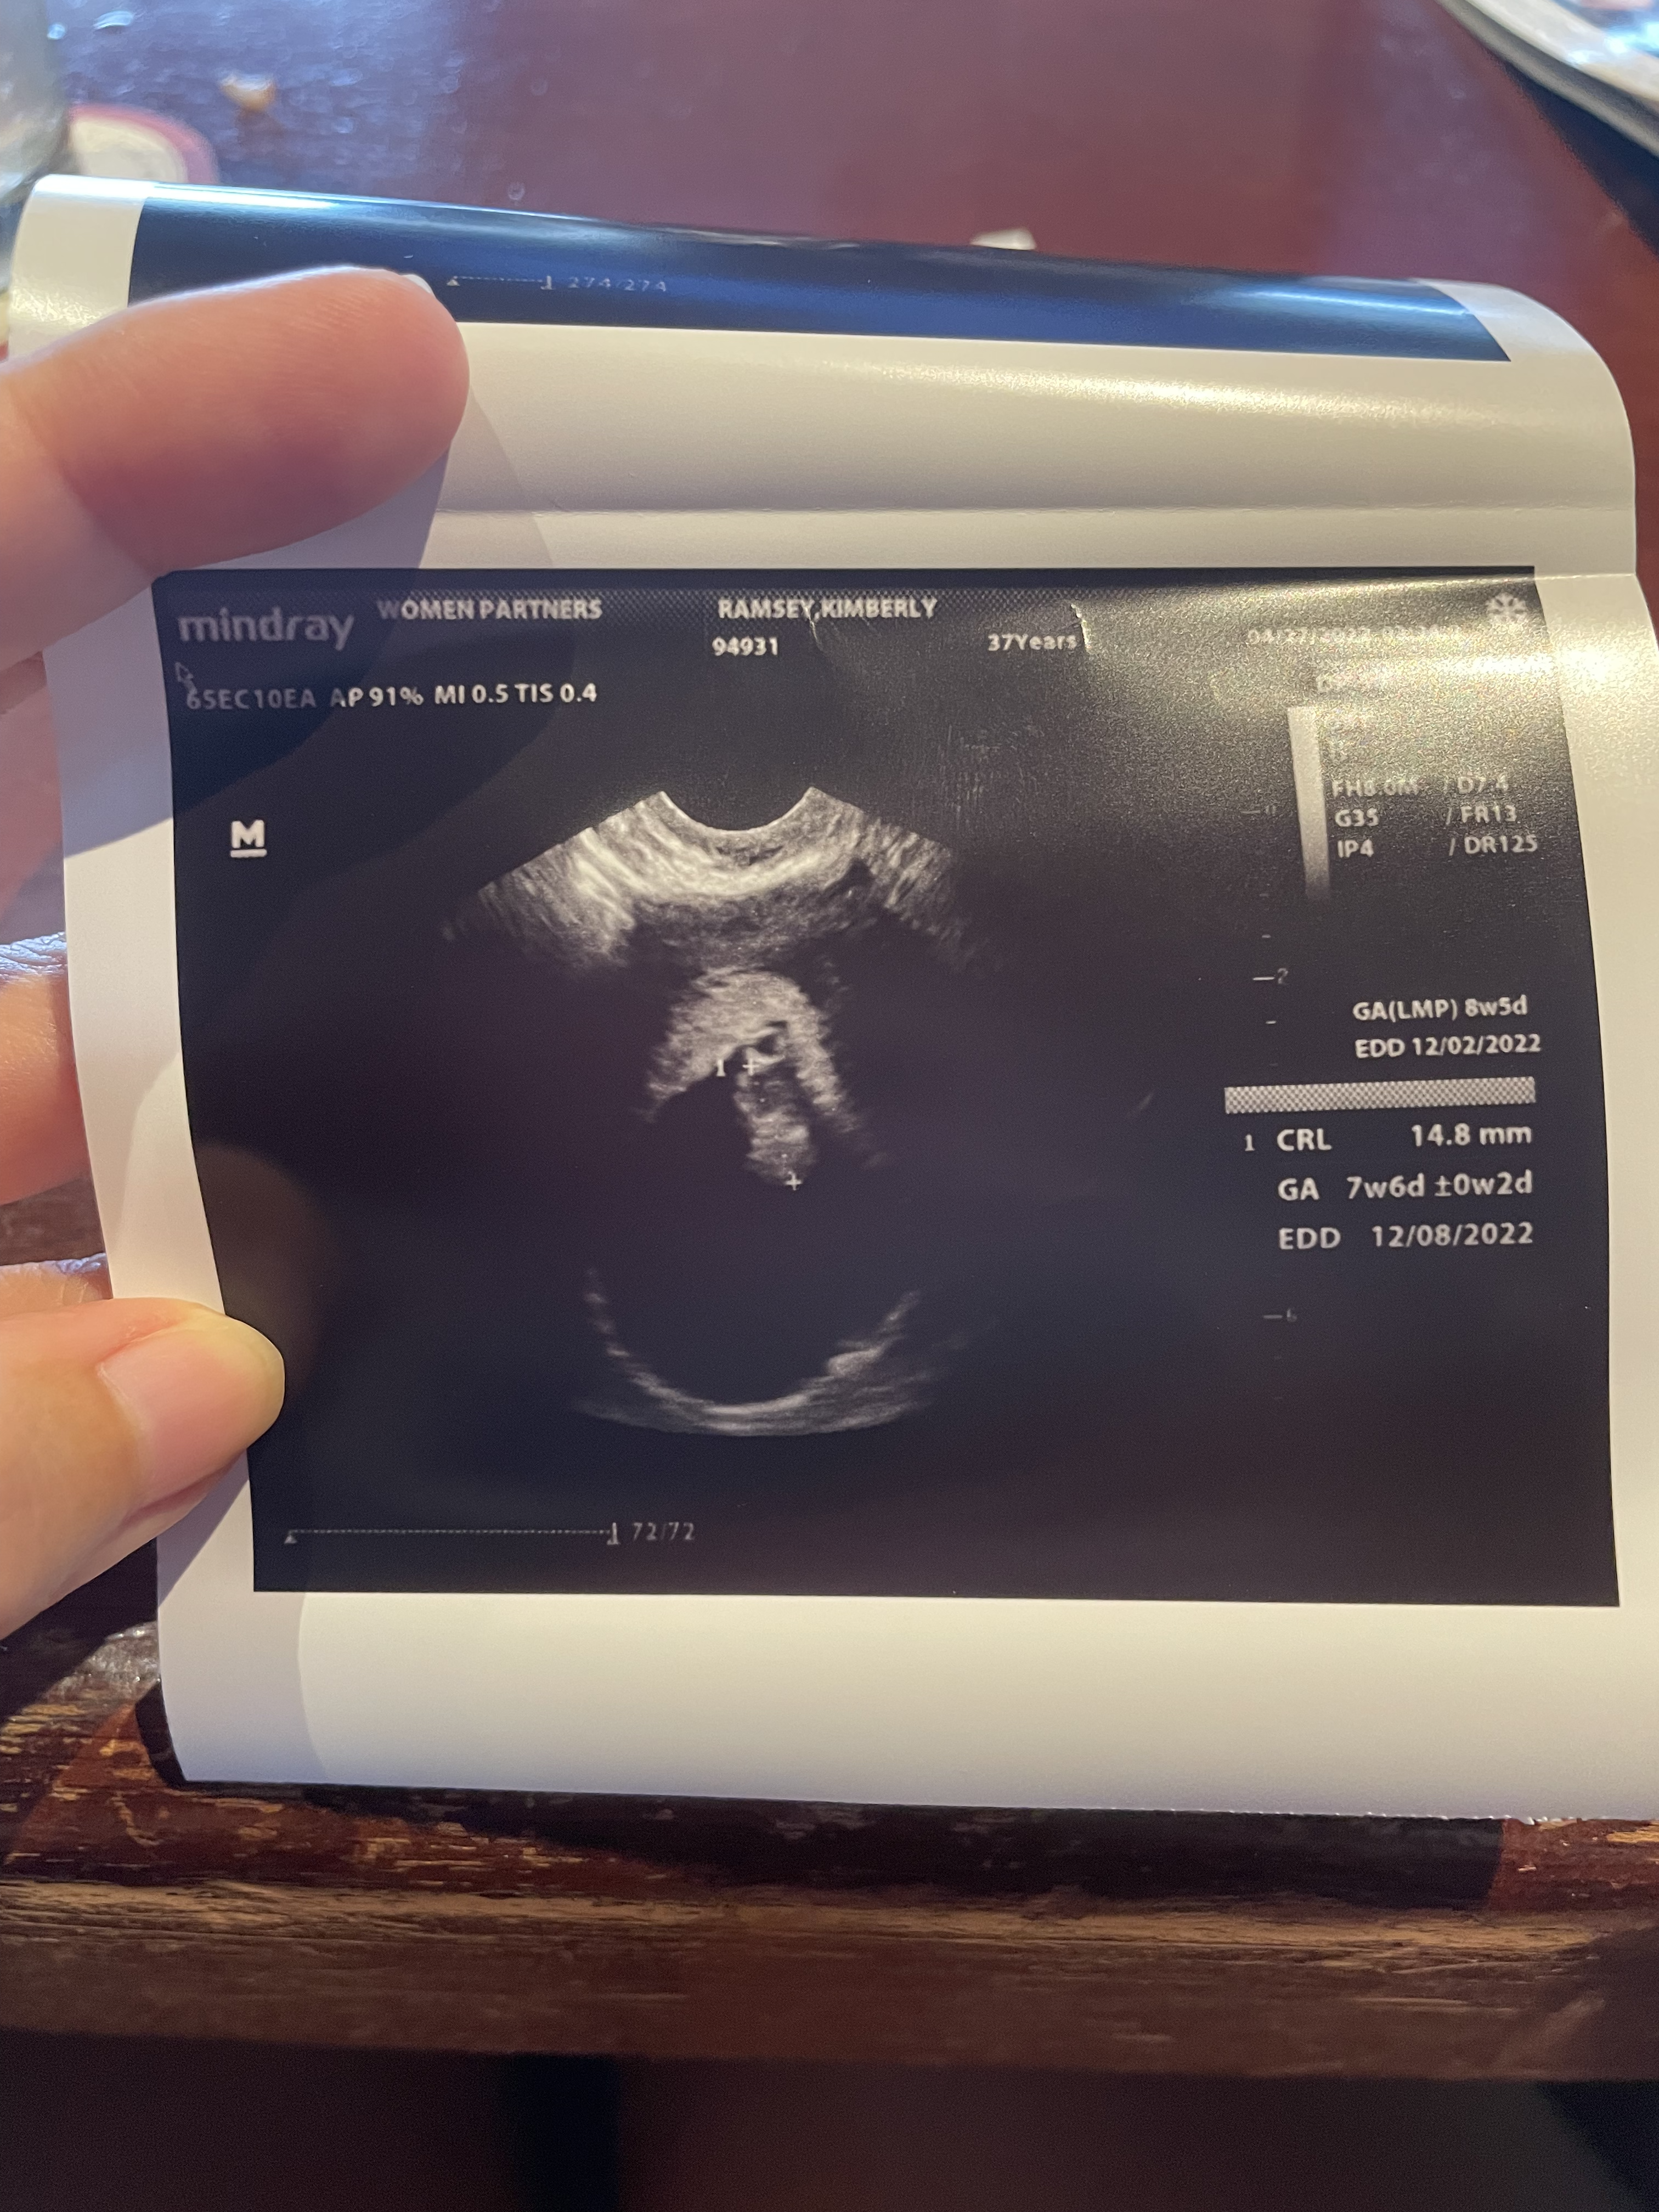

Our First Ultrasound: April 27, 2022

To be honest, even though we had already gotten into baby planning mode, things didn’t feel official until that first ultrasound. The doctor confirmed that we were in fact expecting and that the heart beat was strong!

I had done the math and was guessing that the due date would be December 18th, but the doctor measured her at 8 weeks and gave the official due date as December 6th, 2022.